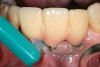

After complete management of moderate to severe periodontitis, including scaling and root planing and in some cases periodontal surgery, subsequent regular periodontal maintenance is reported to prevent tooth loss in up to 85% of patients over a long-term follow-up interval of up to 53 years.6,8 This high success rate of periodontal treatment is comparable to that of dental implants in replacing teeth lost to severe periodontal diseases, highlighting the predictability of maintaining the natural dentition in most patients with periodontal diseases9,10 (Figure 1A and Figure 1B).

Figure 1a  Long-term results of a case involving a 55-year-old woman treated by regenerative periodontal surgery followed by periodontal maintenance every 3 months for 8 years. (A) Radiograph taken in May 2000

Figure 1a

Figure 1b  Long-term results of a case involving a 55-year-old woman treated by regenerative periodontal surgery followed by periodontal maintenance every 3 months for 8 years. (B) radiograph of the same area taken in July 2008.</a></span><P>Figure 1b</P></div>    <div class=